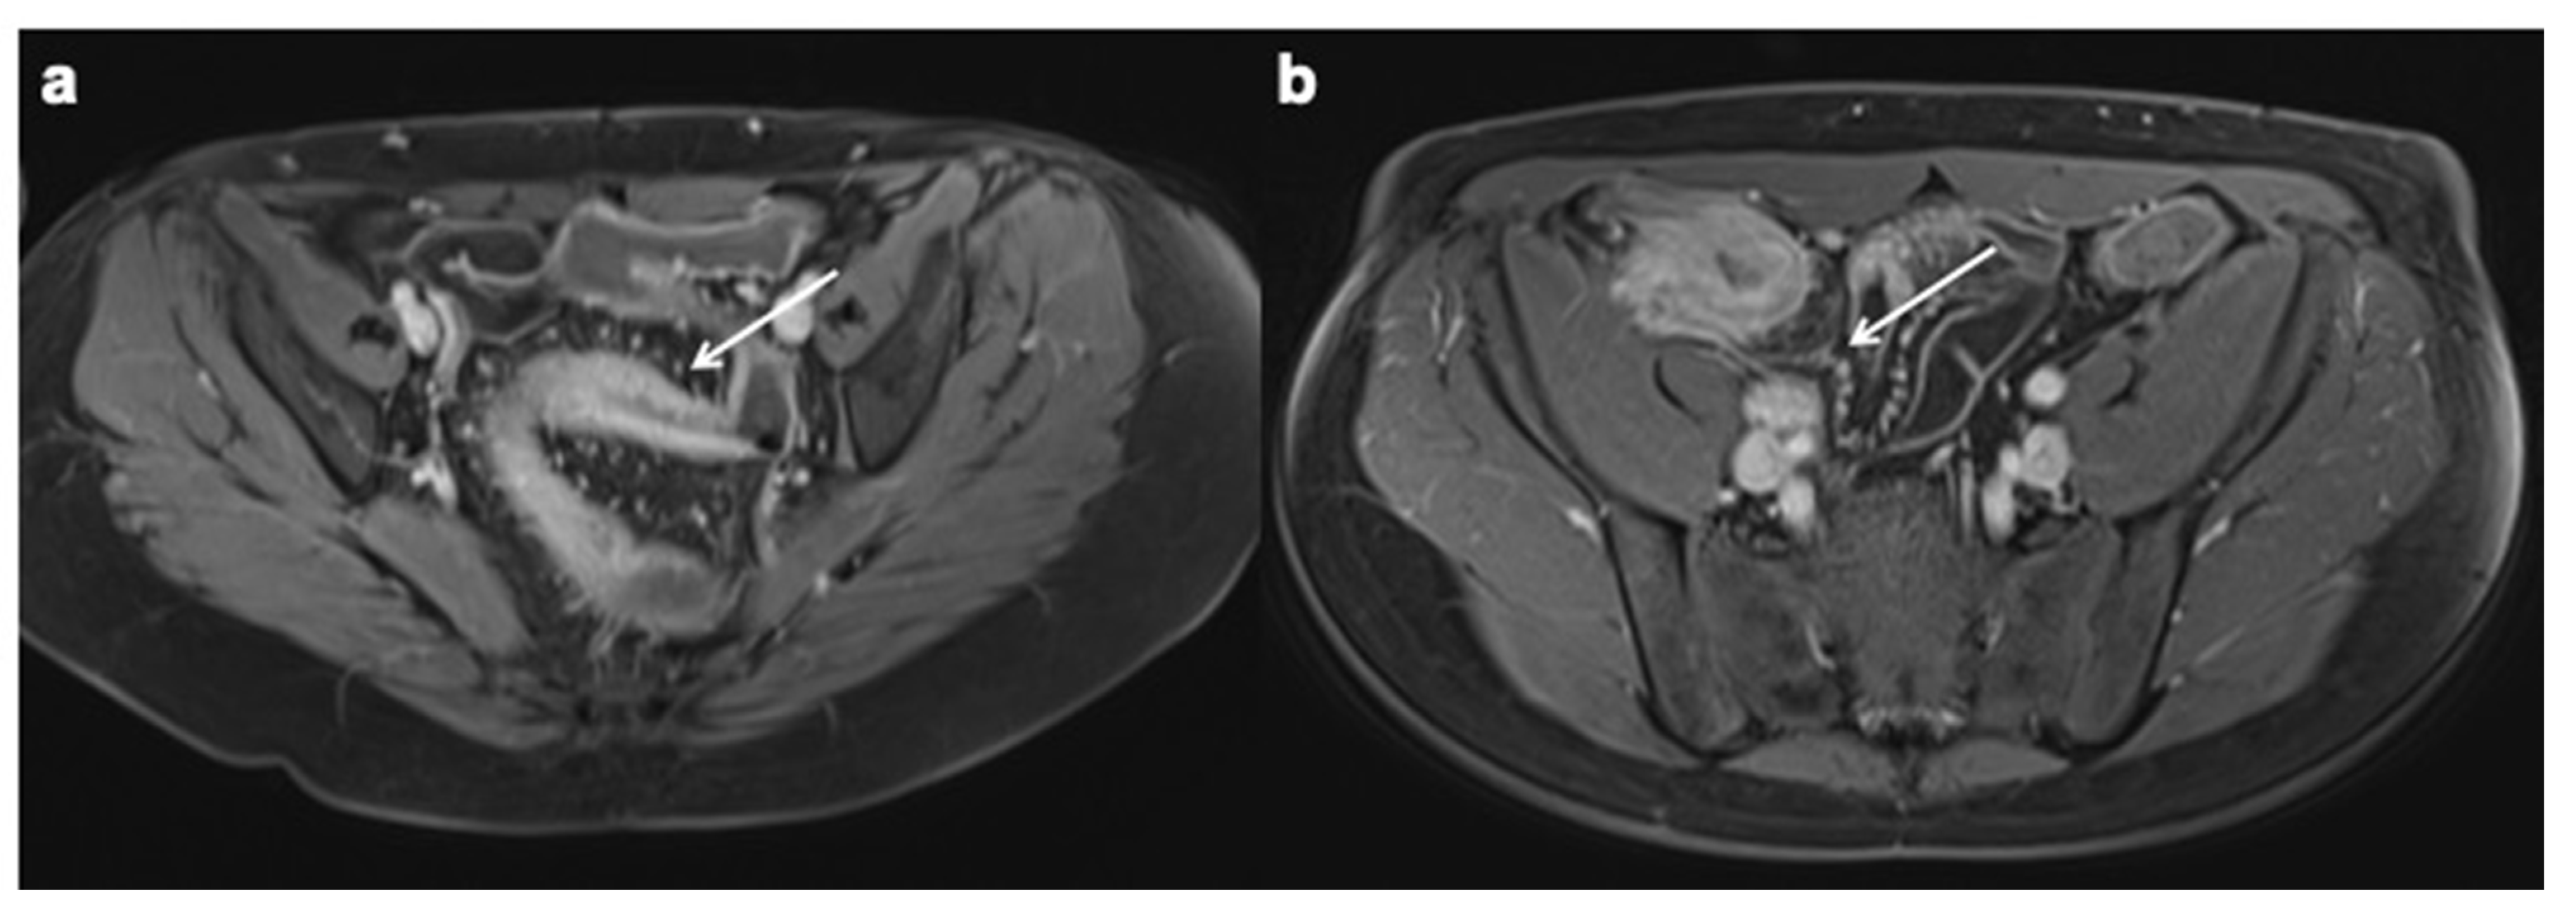

10. Imaging Findings Associated with Active CD Inflammation

11. Imaging Findings Associated with Penetrating CD Inflammation and Complications